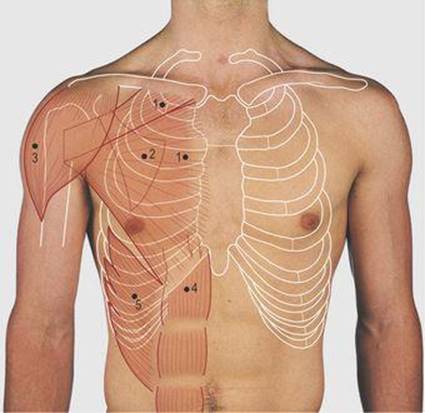

Thoracic incisions and access points (Fig. 4.13)

4.13 Applied anatomy of the anterior chest wall

1 Midline sternotomy approach to the mediastinum

2 Left anterolateral thoracotomy through bed of fifth rib

3 Posterolateral thoracotomy through bed of fourth rib

4 Thoraco-abdominal incision

5 Point for insertion of a needle into ventricles

6 Point for insertion of a needle into pericardial cavity for emergency pericardiocentesis

The ventricles, mitral valve and pulmonary trunk may also be exposed through an incision following the anterolateral aspect of the left fifth rib. The incision passes through skin and subcutaneous tissue onto the rib and the periosteum is divided along the outside of the rib. By stripping the periosteum from the inferior margin of the rib a further incision can be made through the periosteum and parietal pleura in the rib bed to enter the pleural cavity. In this incision the rib is not removed but may be divided posteriorly, or the incision taken transversely across the sternum, to obtain greater exposure.

To expose the hilum of the lung, a posterolateral incision is made through the chest wall with the patient lying on the opposite side and the free arm flexed to pull the scapula forward around the rib cage. The incision follows the line of the fourth rib and fibres of the trapezius and latissimus dorsi muscles are divided in line with the incision (Fig. 4.9, p. 35). Exposure of the posterior mediastinum is through the bed of the seventh or eighth ribs. This incision may be continued across the costal margin to open the abdominal cavity as in operations on the gastro-oesophageal junction.

An intracardiac injection can be made through the medial aspect of the fifth intercostal space. A needle inserted alongside the xiphisternum and passed cranially deep to the body of the sternum will enter the pericardial cavity.

The intercostal nerves run deep to the inferior margin of each rib and they can be anaesthetised by injection of local anaesthetic for pain relief. The site chosen is usually along the posterior axillary line deep to the inferior border of one or more ribs.